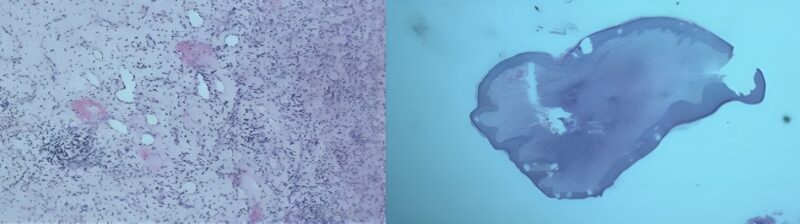

The primary result of the histological examination of the excised lesion suggested a chronic inflammatory process, raising suspicion for atypical mycobacterial infection (AMI) alongside deep fungal infection (Figure 3). Further special staining with PAS, GMS, ZN, and Gram’s stains is recommended to identify the nature of the causative organism.

Figure 3: The primary result of the histological examination, AMI

Histopathological examination of the lesion biopsy confirmed Candida albicans, with susceptibility to voriconazole and itraconazole, and intermediate sensitivity to fluconazole, ketoconazole, and terbinafine. On the third day of hospitalization, the patient continued to have a high-grade fever; therefore, a low dose of corticosteroids was administered to address possible immune-mediated inflammation, resulting in marked clinical improvement. Fever and inflammatory markers normalized within seven days of initiating treatment.